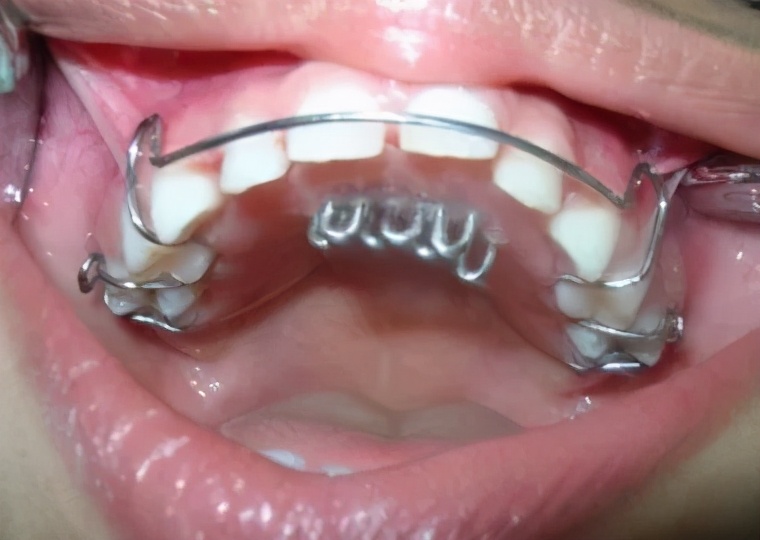

在很少情况下,如果孩子的牙齿很不整齐,而以上方法都不管用,牙医可能会建议在孩子的口腔中安装一个装置,防止手指对上颚或牙齿施加压力。

图源:stopthumbsucking.com